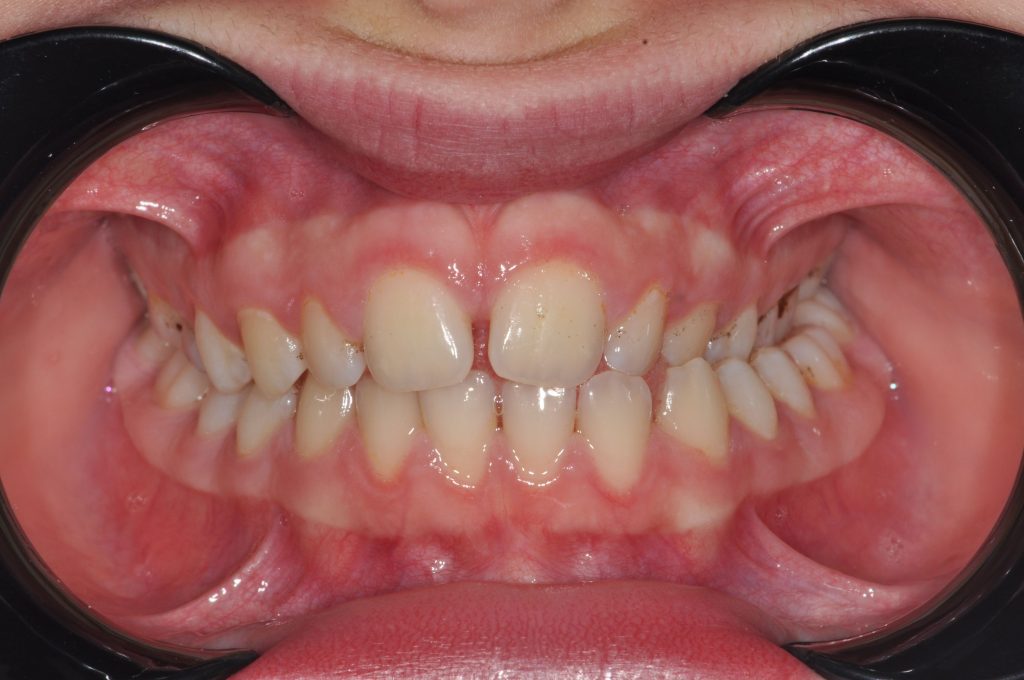

Traitement d’un articulé croisé

Fille de 13 ans

Thérapie avec RPE et bagues de 24 mois

Avant